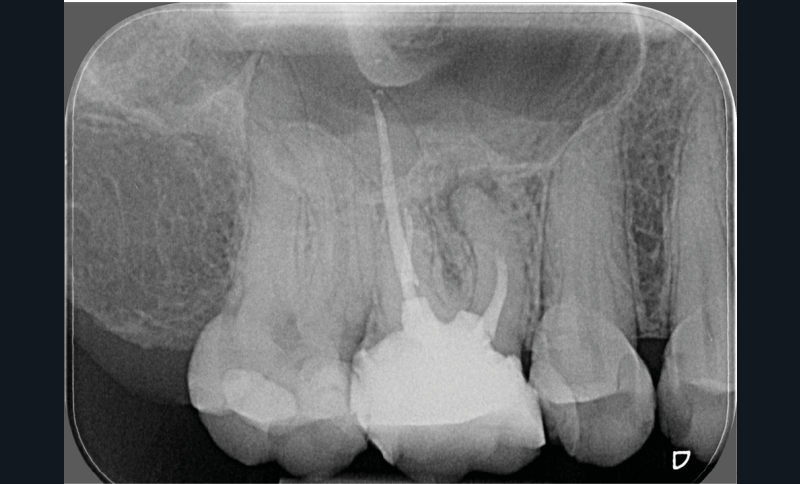

- une pathologie péri-radiculaire ne guérit pas à la suite d’un (re)traitement (fig. 1a-b) ;